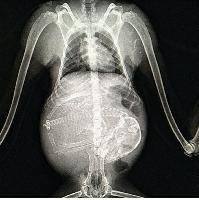

Создание рентгеновского бизнеса для ветеринаров с нуля за 185000 рублей.